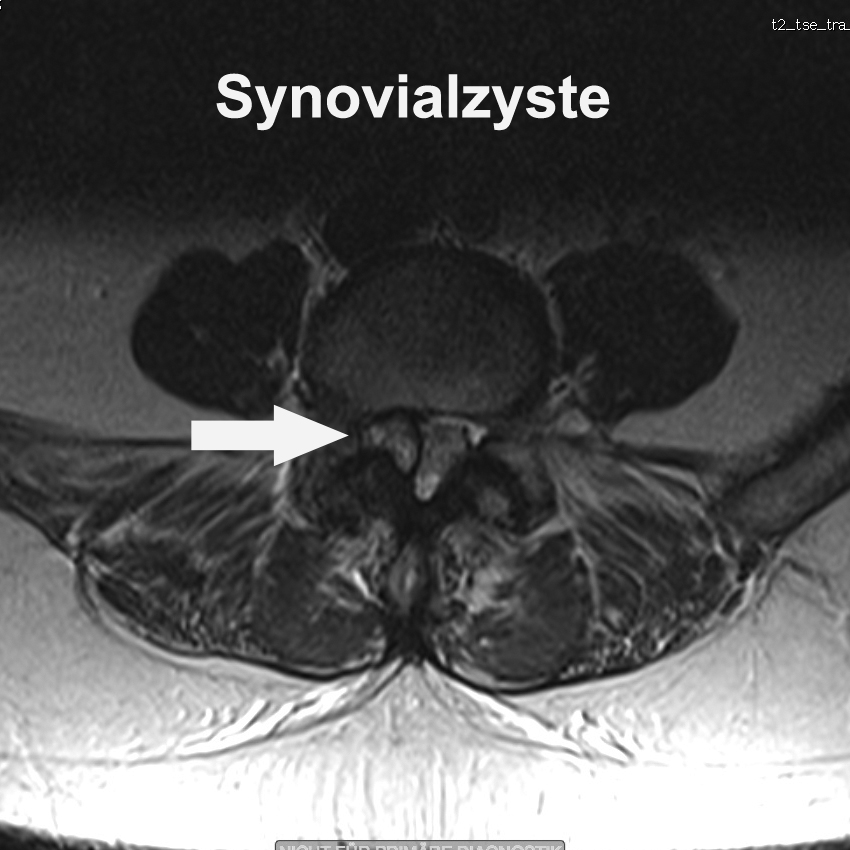

Synovialzysten - Wenn Schleimblasen auf Nerven drücken.

#29

11/09/2025

Wie Gelenkschleim Schmerzen, Taubheit und Nervenstress verursachen kann.

Manchmal reicht eine winzige, schleimgefüllte Blase an der Wirbelsäule, um Nerven richtig auf die Palme zu bringen. Synovialzysten sind gutartig – aber sie können Schmerzen, Taubheit und Gehprobleme auslösen, fast wie ein Bandscheibenvorfall oder Spinalkanalstenose. Wie sie entstehen, warum sie drücken, und was man dagegen tun kann – das erklären wir heute verständlich, mit einem Augenzwinkern und ohne Fachchinesisch